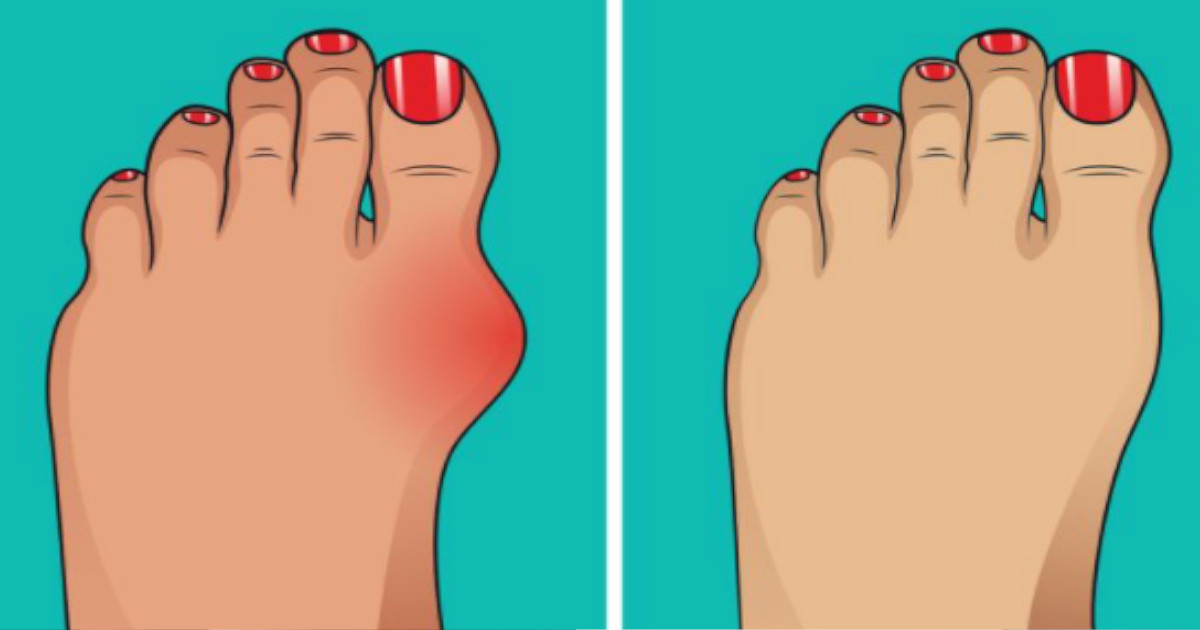

Haluks zazwyczaj przedstawia się jako czerwone lub opuchnięte wybrzuszenie u podstawy dużego palca. Z biegiem czasu paliczki dużego palca mogą stopniowo wystawać dalej na zewnątrz, gdy guz staje się bardziej dotkliwy. Oznaki i objawy haluksa różnią się.

Niezależnie od tego, wszystkie haluksy pojawiają się jako wybrzuszenie u podstawy dużego palca, obolały ból oraz zaczerwienienie i obrzęk w miejscu haluksa są częstymi początkowymi objawami. Ponieważ guz może zwiększyć nacisk wywierany na palce, osoba może również odczuwać drętwienie lub mrowienie.